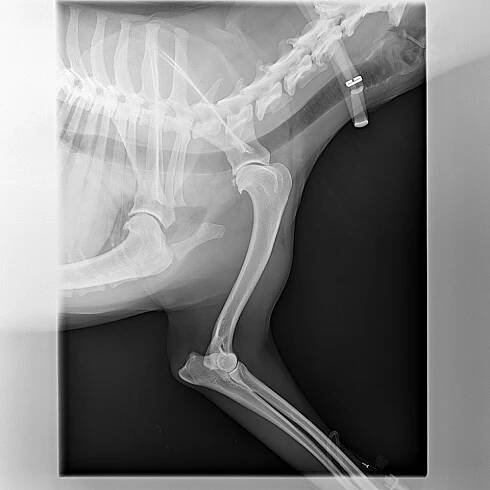

Ulomený osteofyt z kaudálního glenoidu | AnimalClinic